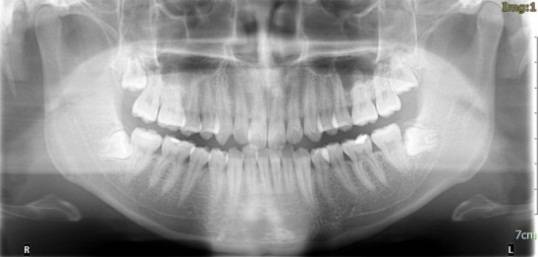

放射检查:一般包括X线头影测量片、曲面体层片和CBCT(锥束CT)。有时还包括其他放射检查,比如螺旋CT等。通过放射检查,医生可以看到骨骼及牙齿的形态、位置及发育状况,以及是否有牙体、根尖周、牙周疾病等,从而评估是否需要正畸治疗、进行何种治疗。

(摘自“第三章第一节正畸的基本知识”)

头影测量片(上)、曲面体层片(中)和锥束CT(下)